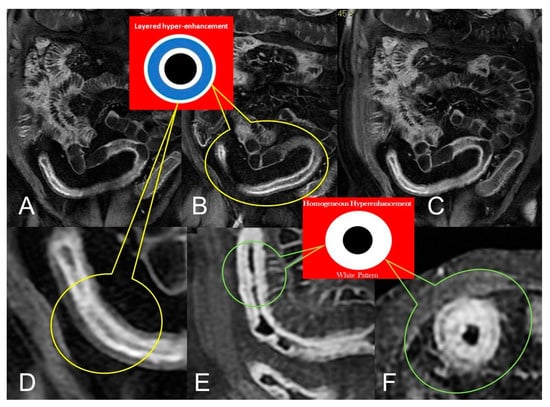

In CD, segmental bowel wall mural hyperenhancement represents the pathological tissue that at contrast-enhanced MRE is revealed as increased mural signal intensity in a small bowel’s segment compared with the normal adjacent intestinal tract [5]. Mural hyperenhancement can be asymmetric (in a small bowel loop, it could involve the mesenteric border more than the antimesenteric one), stratified (bilaminar or trilaminar inner-wall hyperenhancement or halo sign), or homogeneous (evenly distributed over the entire bowel wall). Submucosal edema, granulation tissue, intramural fat accumulation, fibrosis, or inflammatory infiltration may contribute to stratified enhancement (Figure 3 and Figure 4). Bowel wall enhancement evaluation is correctly depicted in the enteric phase (45–50 s after the intravenous contrast material injection begins) and/or in portal venous phase (60–70 s after the intravenous contrast material injection begins). Furthermore, we consider also that endoscopy and histopathological examination clearly show the absence of mucosa in the affected intestinal segments, so the term “mucosal hyperenhancement” is incorrect when the stratified enhancement pattern is expressed and should not be used. Finally, it must be underlined that the segmental bowel wall mural hyperenhancement is a sensitive but non-specific sign of CD, and therefore it must always be contextualized in the general framework of interpretation [6].

In the setting of bowel wall evaluation, a stratified/layered pattern of enhancement is a specific radiological sign of active inflammation in CD [17]; on the contrary, homogeneous slow enhancement on delayed post gadolinium T1W images is indicative of inactive or quiescent disease [18,19,20]. The typical “target sign” of active inflammation is a stratified bowel wall appearance due to mucosal and muscle/serosa increased contrast enhancement with intermediate hypo-intensity of edematous submucosa [21].

In chronic disease, there is a fat deposition in the submucosal layer that appears as hypo-intensity in the thickness of the intestinal wall on T2-weighted images with fat saturation (Figure 4B).

During subacute transmural inflammation, the thickened and fibrotic bowel wall exhibits diffuse and homogeneous contrast enhancement, and the mild mucosal enhancement with hypo-intensity of the deep layers suggests fibrotic condition [19].

In spite of this, stratified or layered enhancement in the intestinal wall, which typically indicates active inflammatory CD, can also exist when fibrostenotic disease coexists with active inflammation. In fact, in patients with small bowel CD, fibrosis and active inflammation sometimes coexist at regions of luminal constriction [18,19,20,21,22].

Thickening throughout the intestinal loop circumference might be eccentric (asymmetric) or circumferential (symmetric) depending on the type of involvement (Figure 16B,C) [29,30]. According to the length of the pathological bowel tract, thickening can be focal, segmental, or diffuse. Bowel thickening is defined as focal when the pathological tract is shorter than 5 cm in length (Figure 17A); segmental thickening refers to 6–40 cm in length of thickened small bowel (Figure 17B), while it is considered diffuse when a large amount of small bowel loops (>40 cm) is affected (Figure 17C) [29,30]. After contrast-medium injection, various patterns of wall enhancement can be described: stratified, white, and gray [30]. Contrast enhancement is classified as stratified when there is hyperintensity of the inner layer (muco-sa), hypointensity of the intermediate layer (submucosa), and hyperintensity of the outer layer (muscle and serosa layers); this is caused by mucosal hyperemia and submucosal edema. If stratified contrast enhancement is associated to fat deposits in the submucosal layer, it is called “fatty halo” sign [30,31].

The white pattern is caused by intestinal wall enhancement that is more than or equal to vein enhancement of the same degree. The gray pattern (diminished or mild enhancement of the bowel wall) occurs when the enhancement of the bowel wall is similar to muscle attenuation on a contrast-enhanced exam [30].